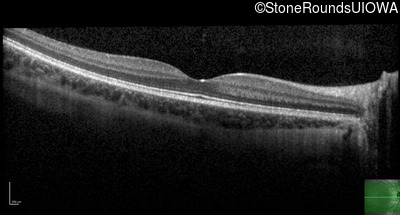

Optical Coherence Tomography - Left - 20/16 -1

Exemplar / OCT Stack